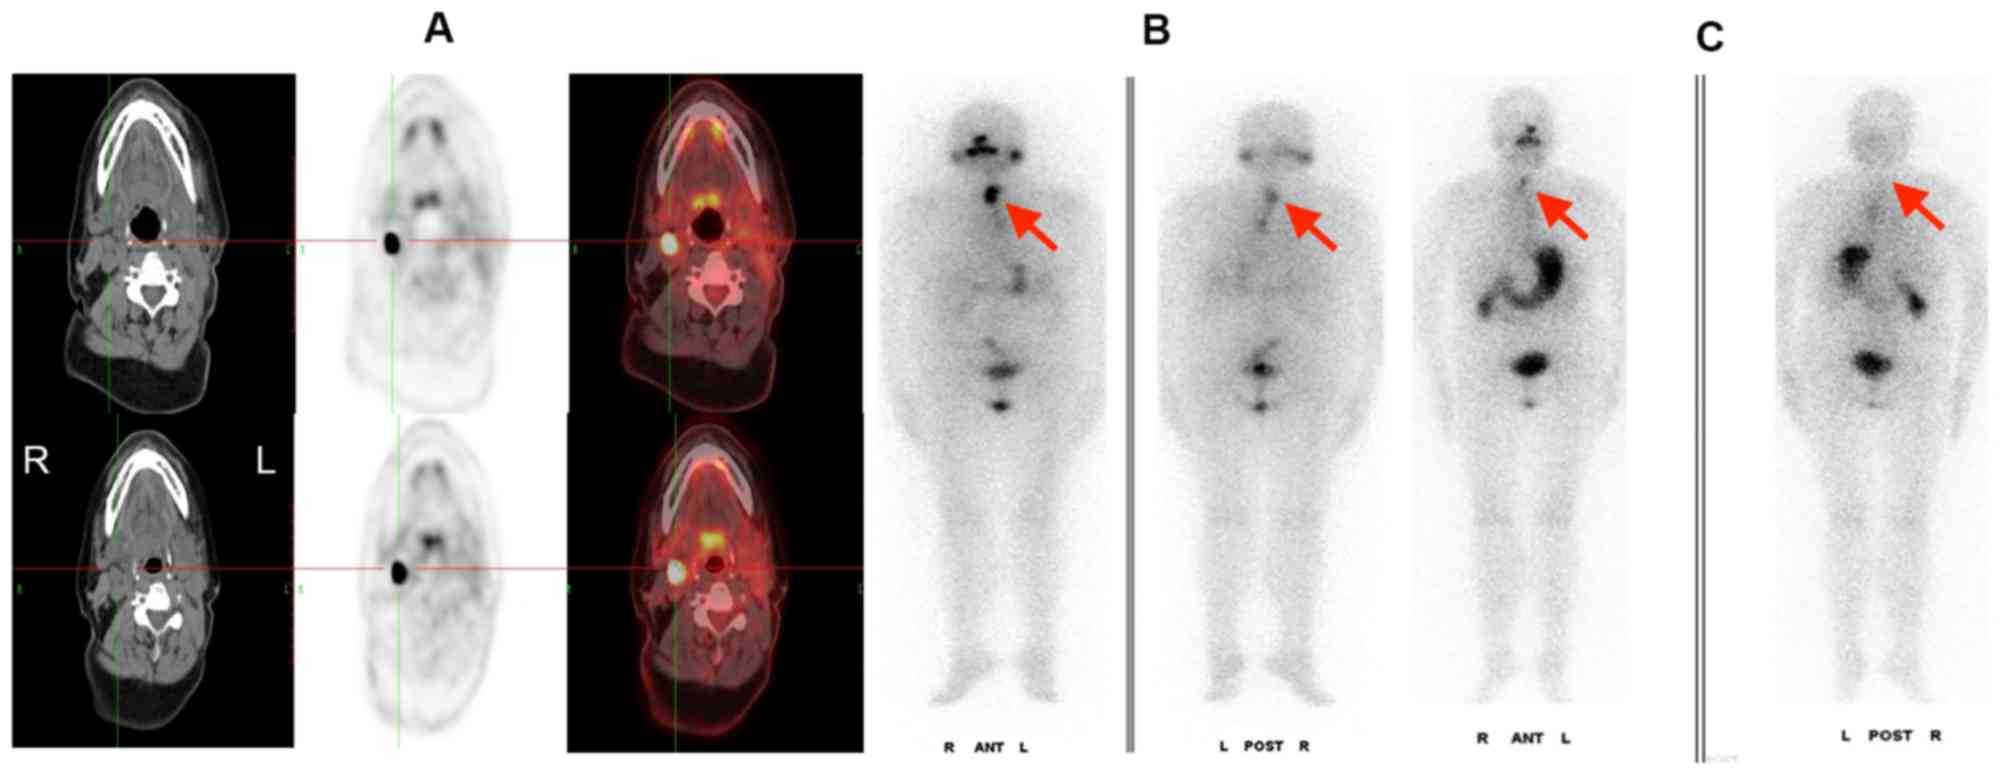

Panel Of 18 F FDG PET CT Imaging At 6 Months Follow up Of Patient 7

https://www.researchgate.net/profile/Brunolf_Lagerveld/publication/286478657/figure/download/fig6/AS:306456508289029@1450076333191/Panel-of-18-F-FDG-PET-CT-imaging-at-6-months-follow-up-of-patient-7-There-are-2-FDG-avid.png

Figure 1 18F FDG PET CT Scanning Identifying Pacing Box Infection With